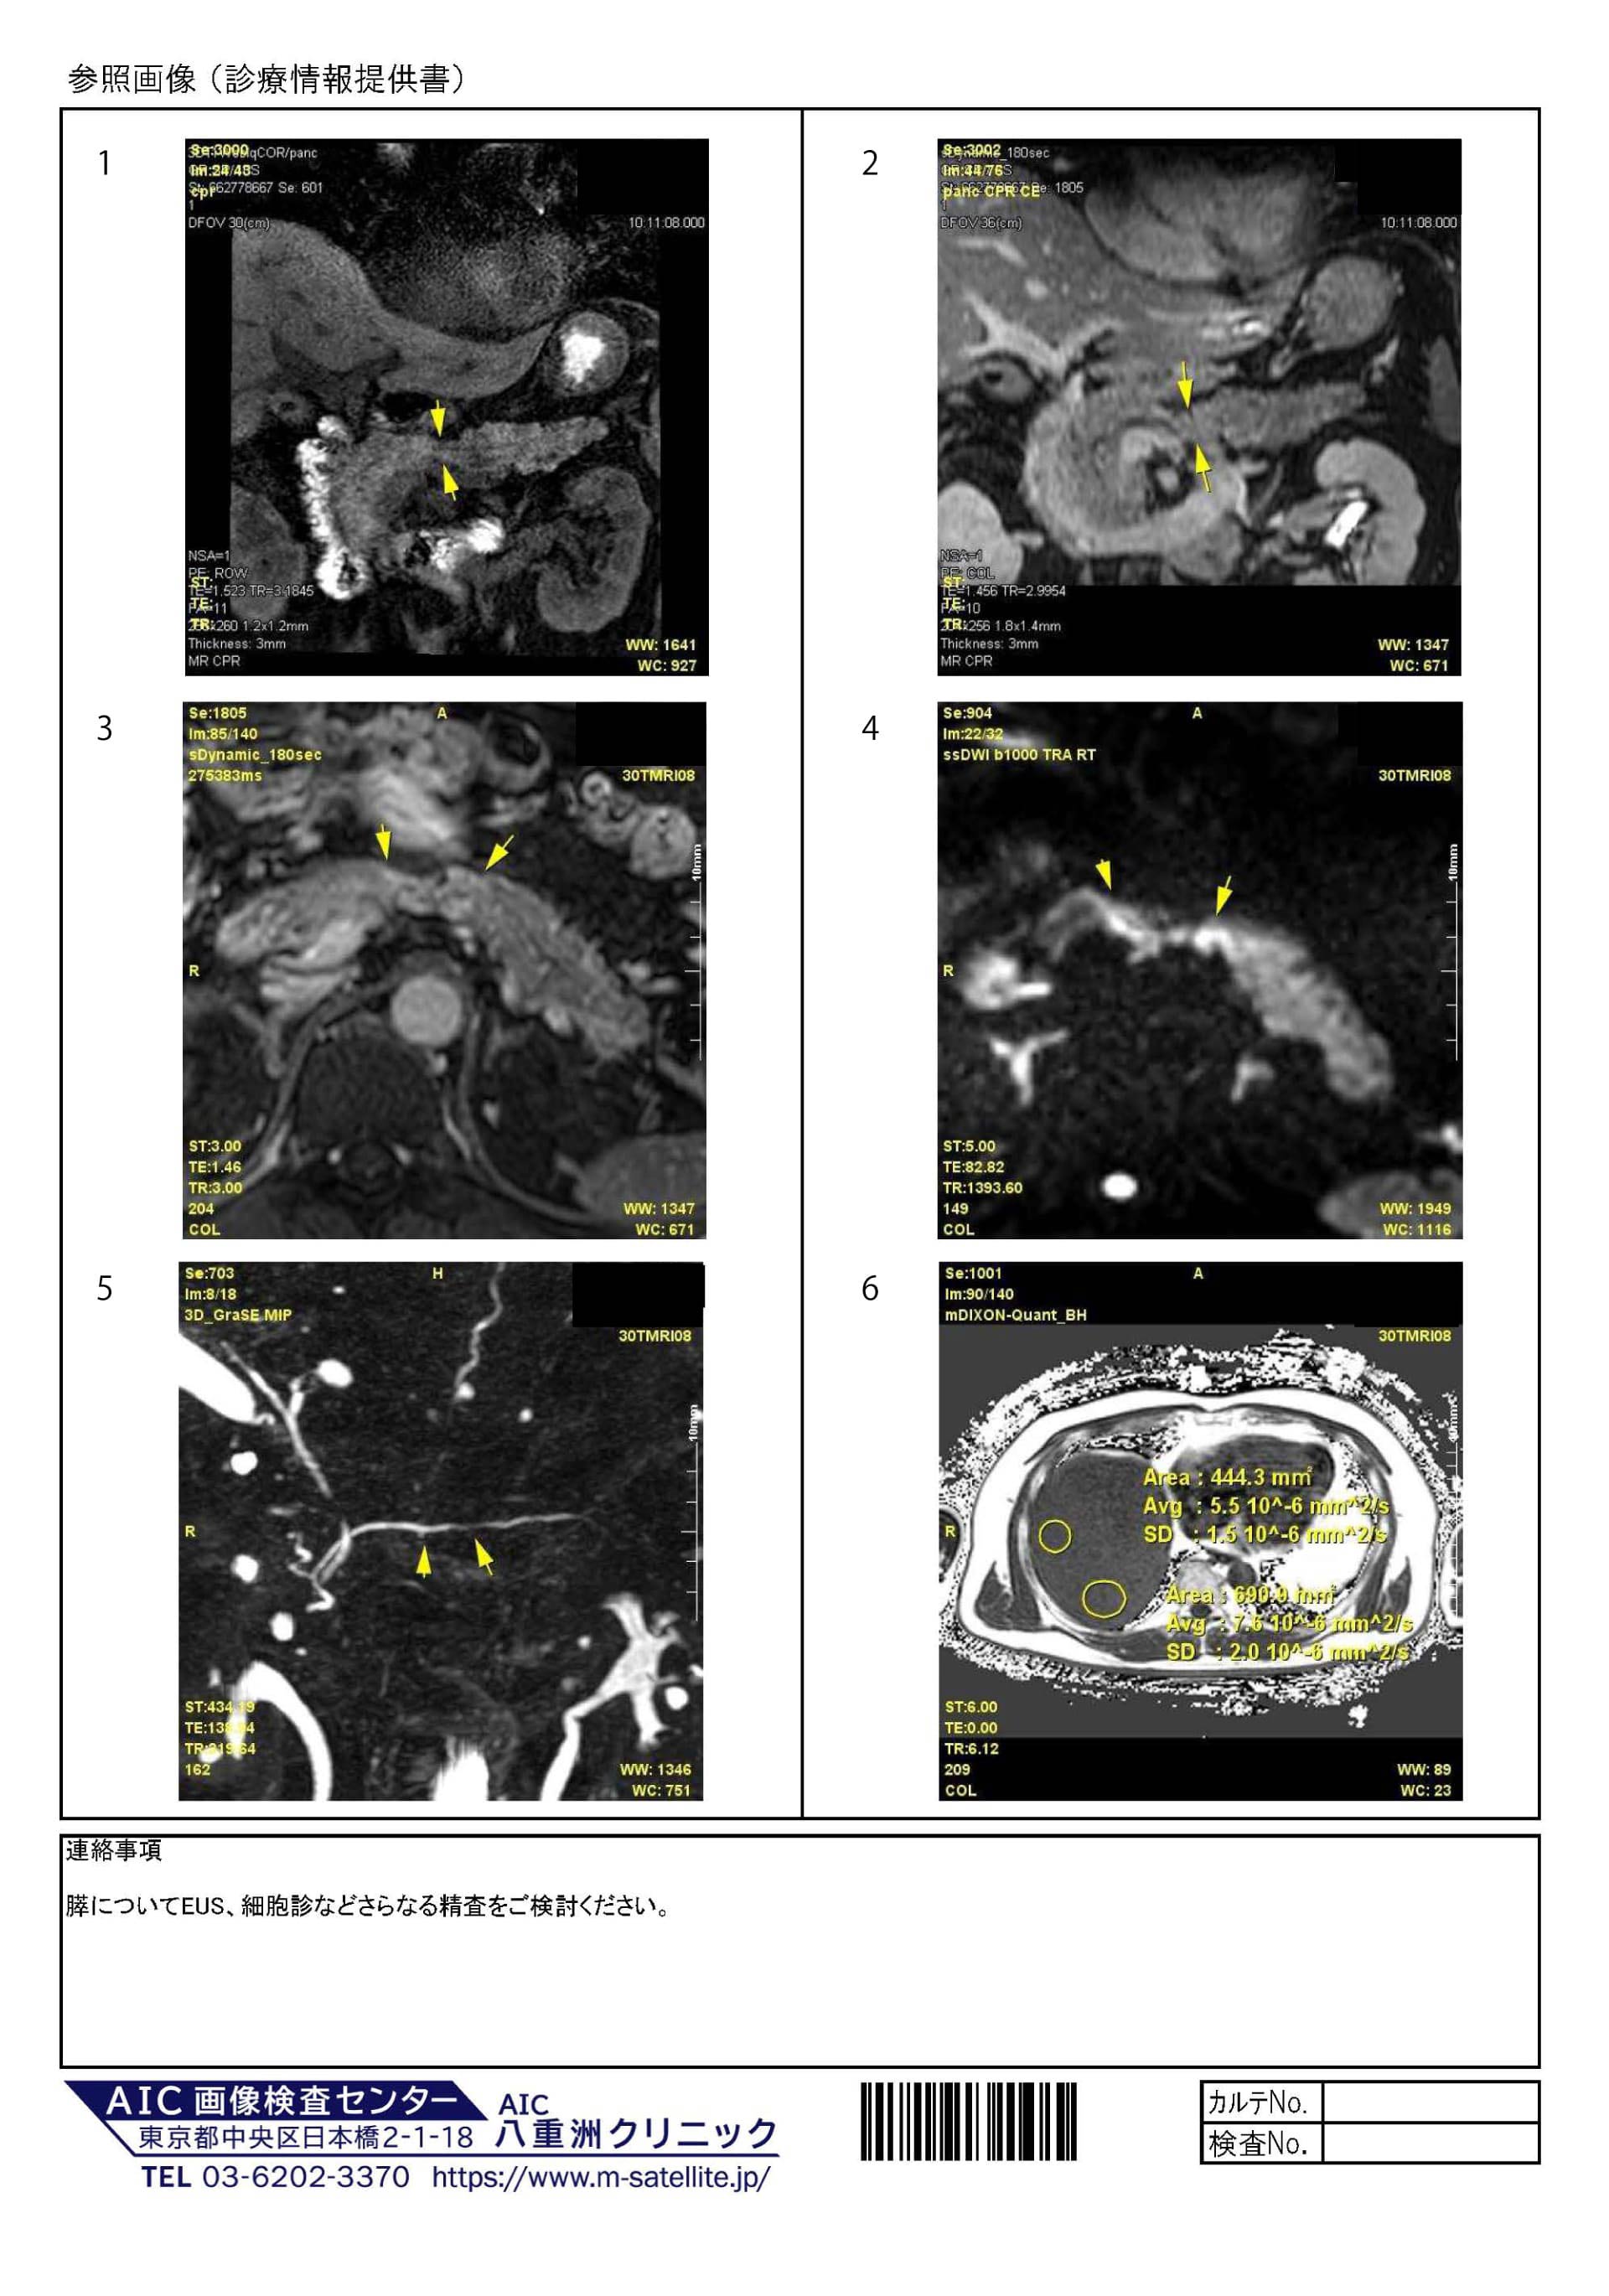

膵実質の不均一萎縮、体部のくびれ状萎縮を認めます。萎縮の程度は著変ありません。(図1)

膵体部のくびれ状萎縮部はDWI高信号で、造影後に遅延性の増強効果が見られます。MRCPでは微小嚢胞と主膵管の軽度狭小化が見られます。これらは以前の検査より明瞭になっています。(図1-5)

肝実質の脂肪含有率は6%程度で軽度脂肪肝です。(図6)

膵体部のくびれ状萎縮+DWI高信号+遅延性増強効果+主膵管狭小化。(図1-5)

:腫瘍初期病変を疑います。EUS、細胞診などさらなる精査をご検討ください。